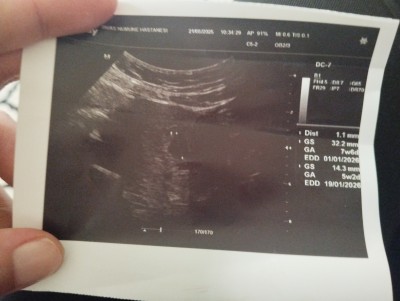

Arkadaşlar merhaba başına gelen var mı merak ettim pazartesi günü özele gittim keseyı gördük 6 mm dedi bugün de devlete gittim normal de 6+1 olmam gerekirken 5+2 gözuktu kese 14 mm dedi bebek yok dedi haftaya tekrardan gel dedi böyle olup bebeği gören var mı moralim bozuldu açıkçası biraz.